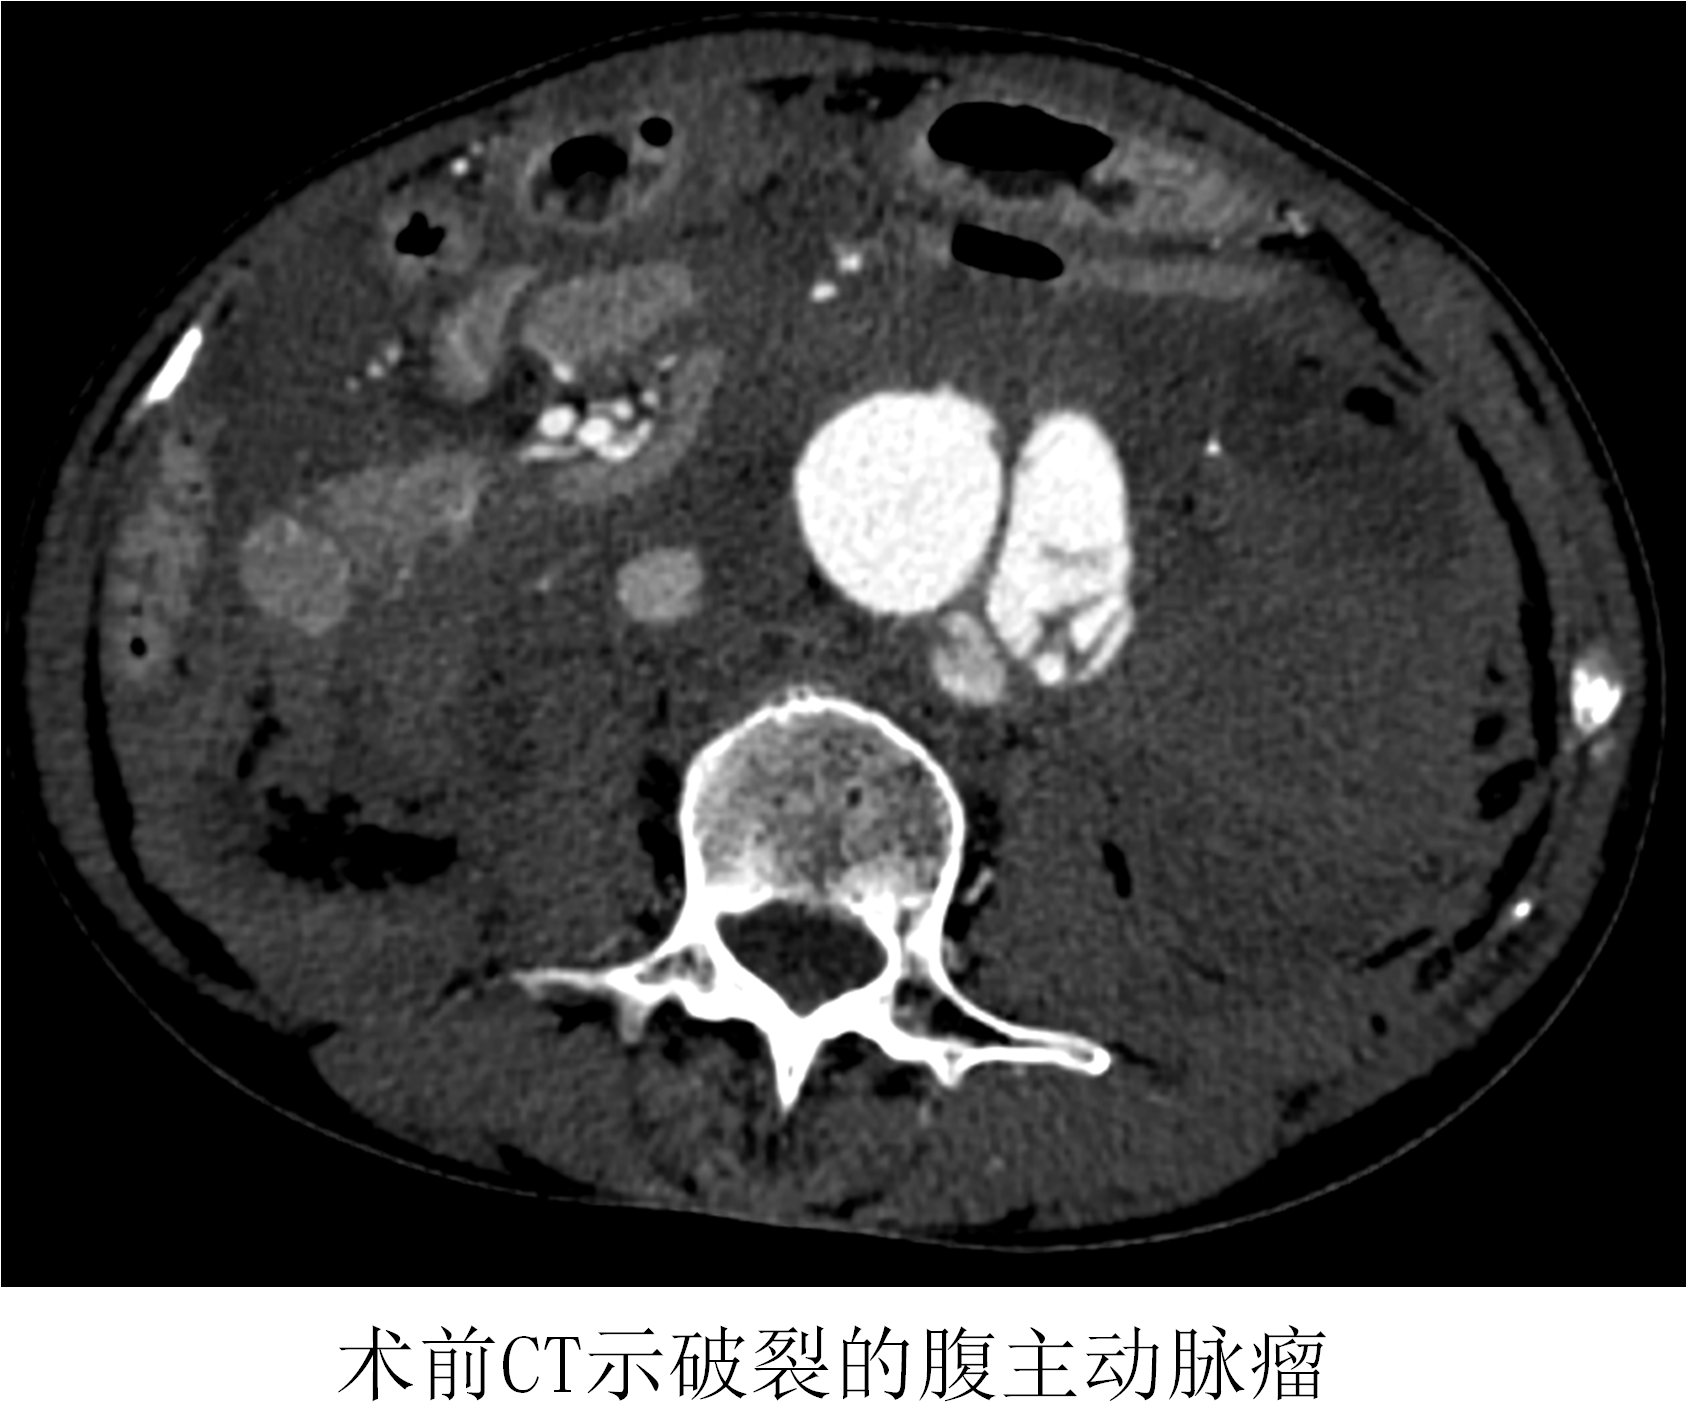

凌晨3點(diǎn),64歲的張女士轉(zhuǎn)至仁濟(jì)醫(yī)院急診時(shí),四肢冰涼、意識不清,心率130次/分,血壓僅70/30mmHg,處于嚴(yán)重休克狀態(tài)。當(dāng)日值班的醫(yī)師李一男和張根潤第一時(shí)間趕到急診,立即開放靜脈通路,補(bǔ)液、輸血抗休克治療,同時(shí)完善術(shù)前檢查和準(zhǔn)備工作。檢查結(jié)果顯示,患者的實(shí)際情況比想象中的還要嚴(yán)重,血紅蛋白已經(jīng)下降到了30g/L,僅是正常人的1/4,也就是說患者腹主動脈瘤破裂出血的量已經(jīng)超過了全身血量的一半以上,如不盡快手術(shù)封堵破口,患者隨時(shí)會有死亡風(fēng)險(xiǎn),可謂是命懸一線。

薛冠華在得知患者情況后,立刻從家中趕往醫(yī)院,開始了這場與死神的賽跑;颊咴诩痹\抗休克治療的同時(shí),半小時(shí)內(nèi)完成所有檢查,隨即被送入復(fù)合手術(shù)室。此時(shí)患者的血壓繼續(xù)下降,最低時(shí)只有60/30mmHg。

時(shí)間就是生命!在來不及全麻的情況下,薛冠華當(dāng)機(jī)立斷,局麻手術(shù)。手術(shù)由薛冠華主刀、倪其泓和王預(yù)立醫(yī)師共同協(xié)助,在麻醉醫(yī)師黃丹、手術(shù)室護(hù)士夏悅和放射科技師馬鋆的配合下緊張進(jìn)行。薛冠華通過精準(zhǔn)定位,在避免影響內(nèi)臟血管的同時(shí),采用腔內(nèi)技術(shù)在短短30分鐘內(nèi)就將腹主動脈瘤的破口通過覆膜支架封堵,有效阻止了進(jìn)一步出血。患者的血壓開始回升,情況逐漸平穩(wěn),手術(shù)順利完成;颊咿D(zhuǎn)入重癥監(jiān)護(hù)室后意識慢慢恢復(fù),術(shù)后10天復(fù)查CT顯示破裂的腹主動脈瘤隔絕良好,已于近期康復(fù)出院。